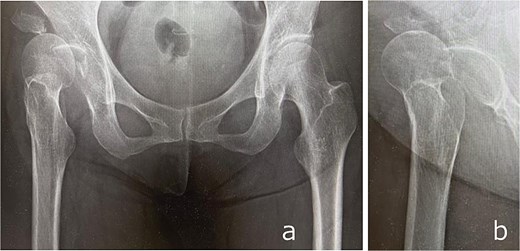

Plain radiographs demonstrated an anterior dislocation of the right hip with associated acetabular fractures (Fig. 1). Computed tomography (CT) after closed reduction revealed fractures of the anterior inferior iliac spine (AIIS), the anterior acetabular wall, and an intra-articular femoral head fracture fragment (Fig. 2). The injury was classified as Pipkin type IV [2] and Brumback type 4B [3].

CT images obtained at initial presentation: Axial (a), coronal (b), and sagittal (c) views, as well as three-dimensional reconstructions (d and e), showing anterior hip dislocation with fractures of the acetabular anterior wall and anterior inferior iliac spine.